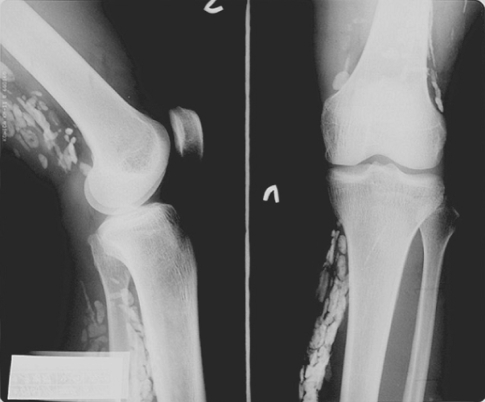

On physical examination, relatively ill defined, variously sized, round or elongated, soft nodules were detected on the medial aspect of her left leg and popliteal fossa. Routine laboratory test results were within reference ranges, and no leukocytosis and no eosinophilia was detected in the peripheral blood. A plain knee radiograph taken at a primary clinic demonstrated multiple discoid calcifications around her knee (Fig. 1). Ultrasonography revealed subcutaneous hypoechoic elongated nodules and irregular intramuscular calcifications in the left lower leg antero-medially with slightly increased peripheral vascularity. Elongated and dilated superficial veins were also identified along the hypoechoic nodule and this showed compressibility at the same time (Fig. 2). Magnetic resonance (MR) imaging revealed a multilocular (tubular and round) subcutaneous lesion (width 45 mm, thickness 15 mm, length 75 mm) in the antero-medial aspect of the proximal left lower leg. The lesion showed low signal intensity on T1 weighted images, high and low signal intensities on T2 weighted images, and irregular thick rim enhancement. Numerous calcific foci were noted along the medial margin of the soleus and medial head of the gastrocnemius muscle. Sporadic intra- and intermuscular calcific foci were also noted at the postero-lateral portion of the distal thigh, which showed faint rim enhancement (Fig. 3). The preoperative diagnosis was made as a partly thrombosed varicose vein associated with myositis at adjacent muscles.

On plain radiographs, calcification has been reported as an important diagnostic clue of cerebral sparganosis (Chang et al., 1992; Dunn and Palmer, 1998). The sonographic findings include a linear echogenicity with a 'dot and dash' pattern in some portion of the tract, which is a highly characteristic finding of sparganosis (Cho et al., 2002). Our patient also disclosed similar findings, but dilated veins along and around mass with compressibility on ultrasonography made us confusing the diagnosis. The live sparganum, with an overlying soft capsule, was misinterpreted as a partly thrombosed varicose vein. MR images of muscular sparganosis are conglomerated cystic lesions and reactive changes in the adjacent soft tissues. The imaging appearance of the cystic lesions with surrounding reactive changes may resemble pyogenic infections, other parasitic infections (cysticercosis and paragonimiasis) or hemangioma, and these must be differentiated. Moreover, if serpiginous tubular tracts are observed during imaging studies, musculoskeletal sparganosis should be included in the differential diagnosis (Cho et al., 2002). Laminated calcospherules in the cytoplasm of proliferating macrophages and giant cells are of diagnostic value if no sparganum worm is present in a lesion (Chi, 1980).